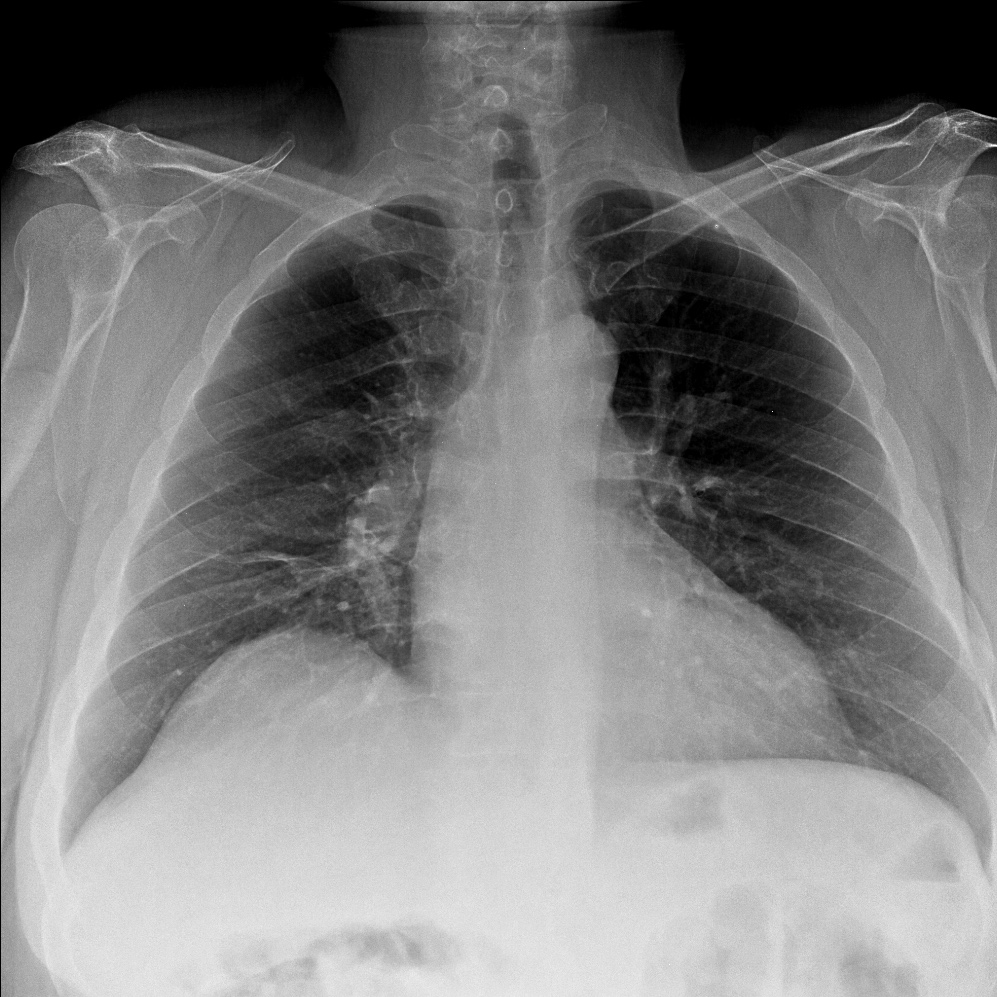

CASO: sospecha de neumonía.

Hallazgos:

- En un principio podríamos decir que existe un aumento de densidad retrocardiaco que podría ser compatible con condensación neumónica a dicho nivel, sin embargo estamos ante una placa poco inspirada, lo cual puede llevarnos a cometer errores diagnósticos.

- Se recomendó volver a realizar la radiografía, observar a continuación:

Ya no se observa el aumento de densidad retrocardiaco, la placa es normal.

INSPIRACIÓN: Una placa bien inspirada es aquella en la que se observar 6-7 arcos costales anteriores o 10-11 arcos costales posteriores. Lo contrario puede producir imágenes falsas de condensaciones o de seudocardiomegalia.